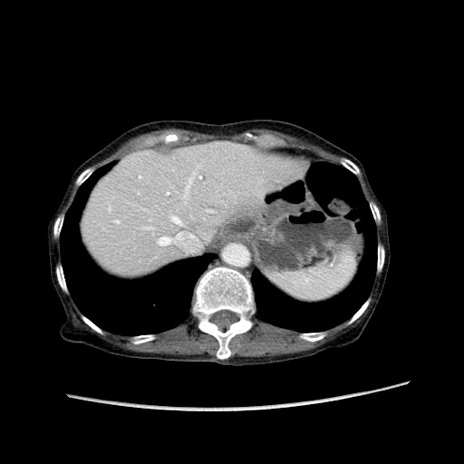

症例25(横断像)

【症例】80歳代女性

【主訴】胸のつかえ感

【現病歴】約9時間前に食後から胸のつかえた感じあり、嘔吐あり、来院。

【既往歴】胃癌(全摘)、胆摘、虫垂炎

【身体所見】心窩部に圧痛あり、反跳痛なし。

【データ】WBC 5700、CRP 0.05